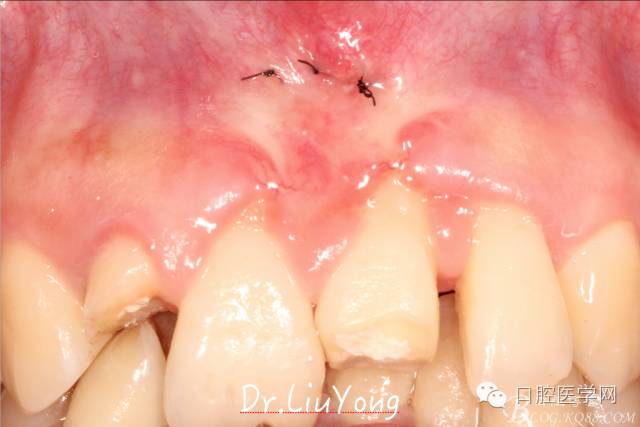

上唇系帶手術(shù)后一周拆線,如上圖:

通過根向復(fù)位瓣術(shù)解決上唇系帶的附著問題